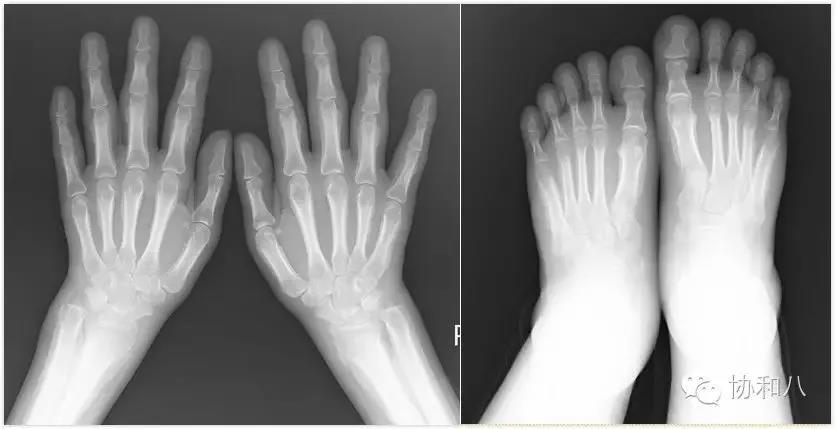

2015 年 10 月,就诊于我院,双手及双足正斜位 X 线:双手足骨质改变,考虑为厚皮质骨病。胸部 HRCT 示脊柱侧弯,左侧少量胸水及胸膜增厚。疼痛明显,先后予乐松、依托考昔、双氯芬酸止痛治疗,效果欠佳。体重下降 15 kg。

营养不良,体型消瘦,强迫体位,痛苦面容。左侧胸壁压痛明显,拒按。胸廓不对称,左侧胸廓塌陷。左侧呼吸活动度减低。叩诊左肺浊音。左肺呼吸音减低,可闻及胸膜摩擦音。心腹(-)。脊柱右突性侧弯。双腕、双膝、双踝关节肿胀,全身多关节压痛。双手双足可凹性水肿。可见杵状指(趾)。双侧膝关节凉髌征消失、浮髌征(+)。

全身骨显像:四肢长骨及左侧肋骨放射性摄取增高,四肢长骨骨皮质增厚。